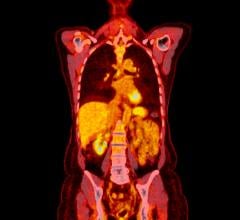

Near-infrared fluorescence targets tissues by hitting them with near-infrared light energy that is absorbed by fluorophores — components of a molecule that make it fluorescent — and then emitted at a longer wavelength (fluorescence). Researchers can detect fluorescence signals by studying the wavelengths of light energy that is released from the tissues. This method can be used to evaluate patients for a range of diseases, such as cancer and Alzheimer’s disease, as well as cardiovascular disease, like deep vein thrombosis (DVT).

In conjunction with the new near-infrared fluorescence fibrin-targeted peptide, investigators were able to successfully detect fibrin-rich deep vein thrombosis with both intravital fluorescence microscopy and noninvasive fluorescence molecular tomography, which allows researchers to acquire information about tissues by analyzing how light is absorbed by and scattered from tissues. By coupling the fibrin peptide agent (EP-2104R) with rapidly emerging intravascular NIRF imaging, researchers now have the opportunity to study micro-thrombi on coronary artery plaques and coronary stents that are at especially high risk for thrombosis and vessel occlusion, the main cause of heart attacks. This could help clinicians predict potential heart attacks and other major cardiovascular events before it is too late, thus potentially saving the lives of patients.